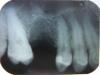

Михаил Л Опубликовано 12 мая, 2010 Автор Поделиться Опубликовано 12 мая, 2010 Выкладываю снимок 5ки зуб давно удален? если да, то обратите внимание на цвет десны , если ярко красная значит воспалена, купите в аптеке противовоспалительные травы (шалфей , ромашка, кора дуба, зверобой) и полоскайте рот. Как давно болит? и с чем связываете данное заболевание? Удален 10 месяцев назад, болело еще до удаления, 6ка была чувствительна при постукивании. Ссылка на комментарий

zybnaya feya Опубликовано 14 мая, 2010 Поделиться Опубликовано 14 мая, 2010 (изменено) Выкладываю снимок 5киУдален 10 месяцев назад, болело еще до удаления, 6ка была чувствительна при постукивании.У вас проблема в 5 зубе. Там уже и изменения в костной ткани есть. Делайте эндо 5ки и протезируйтесь(имплантируйтесь). Пора уже Изменено 14 мая, 2010 пользователем zybnaya feya Ссылка на комментарий